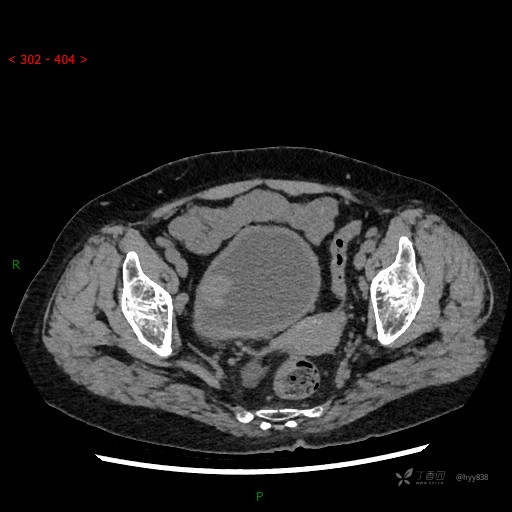

辅助检查:CT

膀胱CT平扫(2022.10.20)